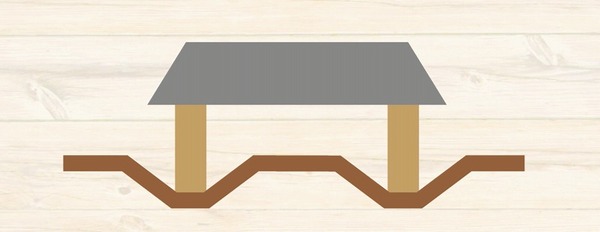

ところが

歯を支えている骨

家をイメージすると

柱を支えている地盤

1本1本の柱を支える地盤しか

もともとないわけです。

ブリッジ治療をした場合には

その歯の根っこの周囲の地盤には

本来受ける何倍もの力が実はかかっています。

つまり

地盤沈下が起こってしまうのです

ブリッジ治療をされた方の場合は

噛む時に無理な力がかからないように注意が必要です。

ブリッジ治療をされた方は

「噛むと地盤沈下を起こす」という危険性を知らされないまま

日常生活を過ごされている方

非常に多いです。